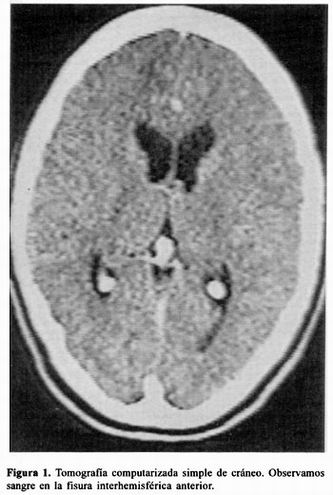

CASUISTICA SÍNDROME PERDEDOR DE SAL CEREBRAL TRAS LA CIRUGÍA ...

El síndrome perdedor de sal cerebral (SPSC) es una complicación frecuente, única alteración un recuento de glóbulos blancos de 13.900 elem/mm3 con desviación a la izquierda, el cirugía de aneurisma de la ACMD presentó marcada ... Document Retrieval

Ción con sospecha de aneurisma cerebral complicado. Al ingreso se mostró hemodinámicamente estable, afebril, con GCS de 15/15, posterior derecha de 8.5 y 2 mm de diámetros máxi-mos, con proyección posterior (Fig. 4). Se realizó su ... Read Here